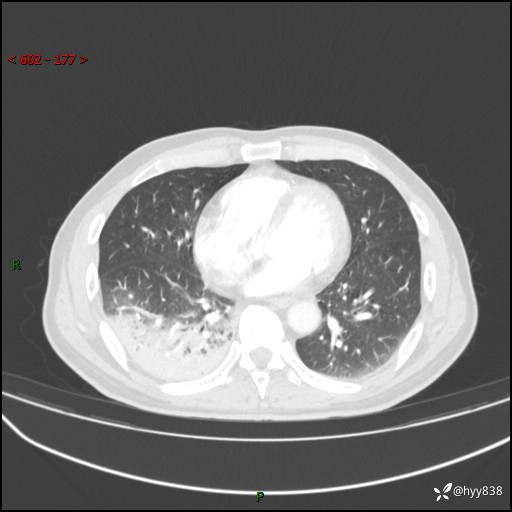

63岁/男,发热5余天。精彩好病例,“大叶性肺炎”,等你来诊---结果公布~

【患者信息】:63岁/男

【主诉】:发热5余天

【现病史及既往史】:患者5余天无明显诱因出现畏寒寒战发热,最高体温39.5℃,发热无明显昼夜规律,伴全身乏力、头晕,无头痛、无咳嗽咳痰、无胸痛咯血、无气短、无腹痛腹泻、无尿频尿急尿痛等不适,于当地市第五人民医院就诊,予以抗感染等治疗(具体不详)后发热无明显好转,1天前查胸部CT提示右下肺感染,为求进一步诊治,门诊以“社区获得性肺炎”收治入院; 起病以来,患者精神、食欲一般,睡眠可,大小便正常,体力体重较前无明显变化。

【检查】:胸部CT增强